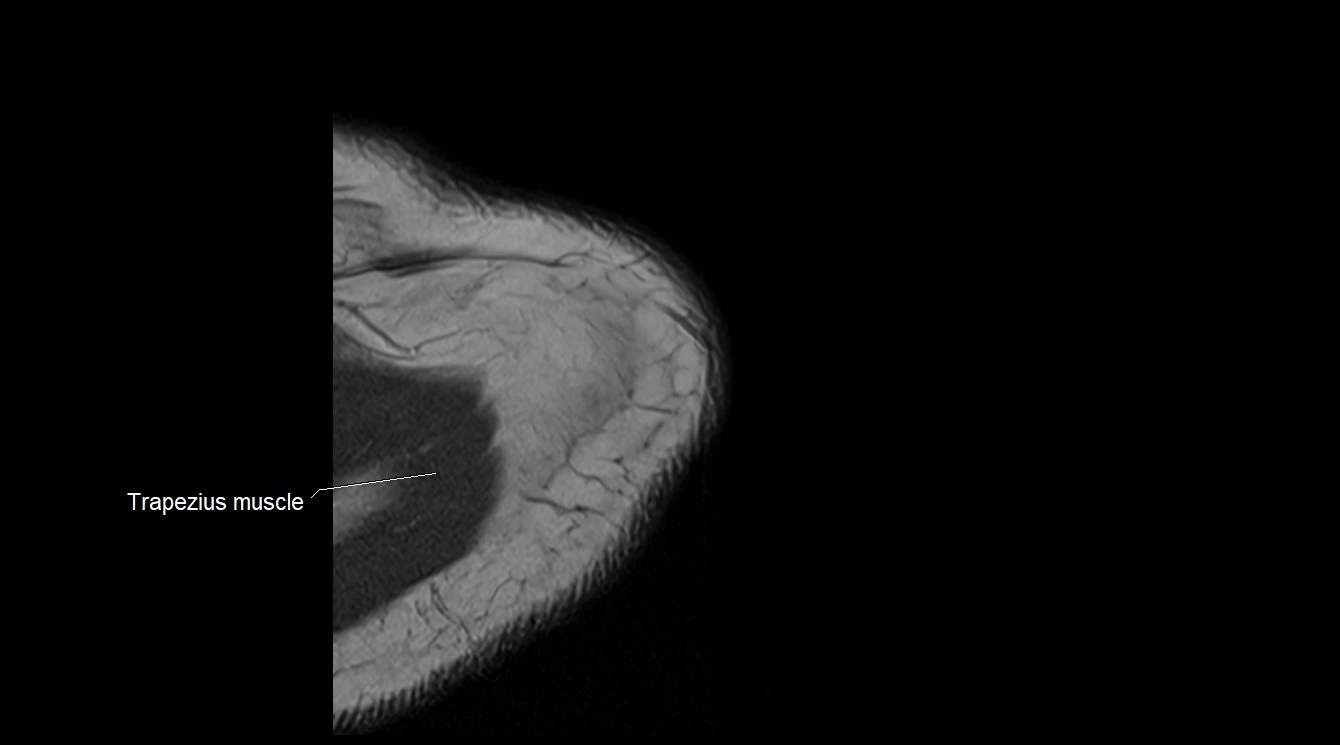

MRI image